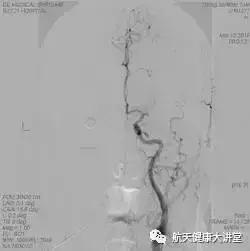

取栓前

取栓后